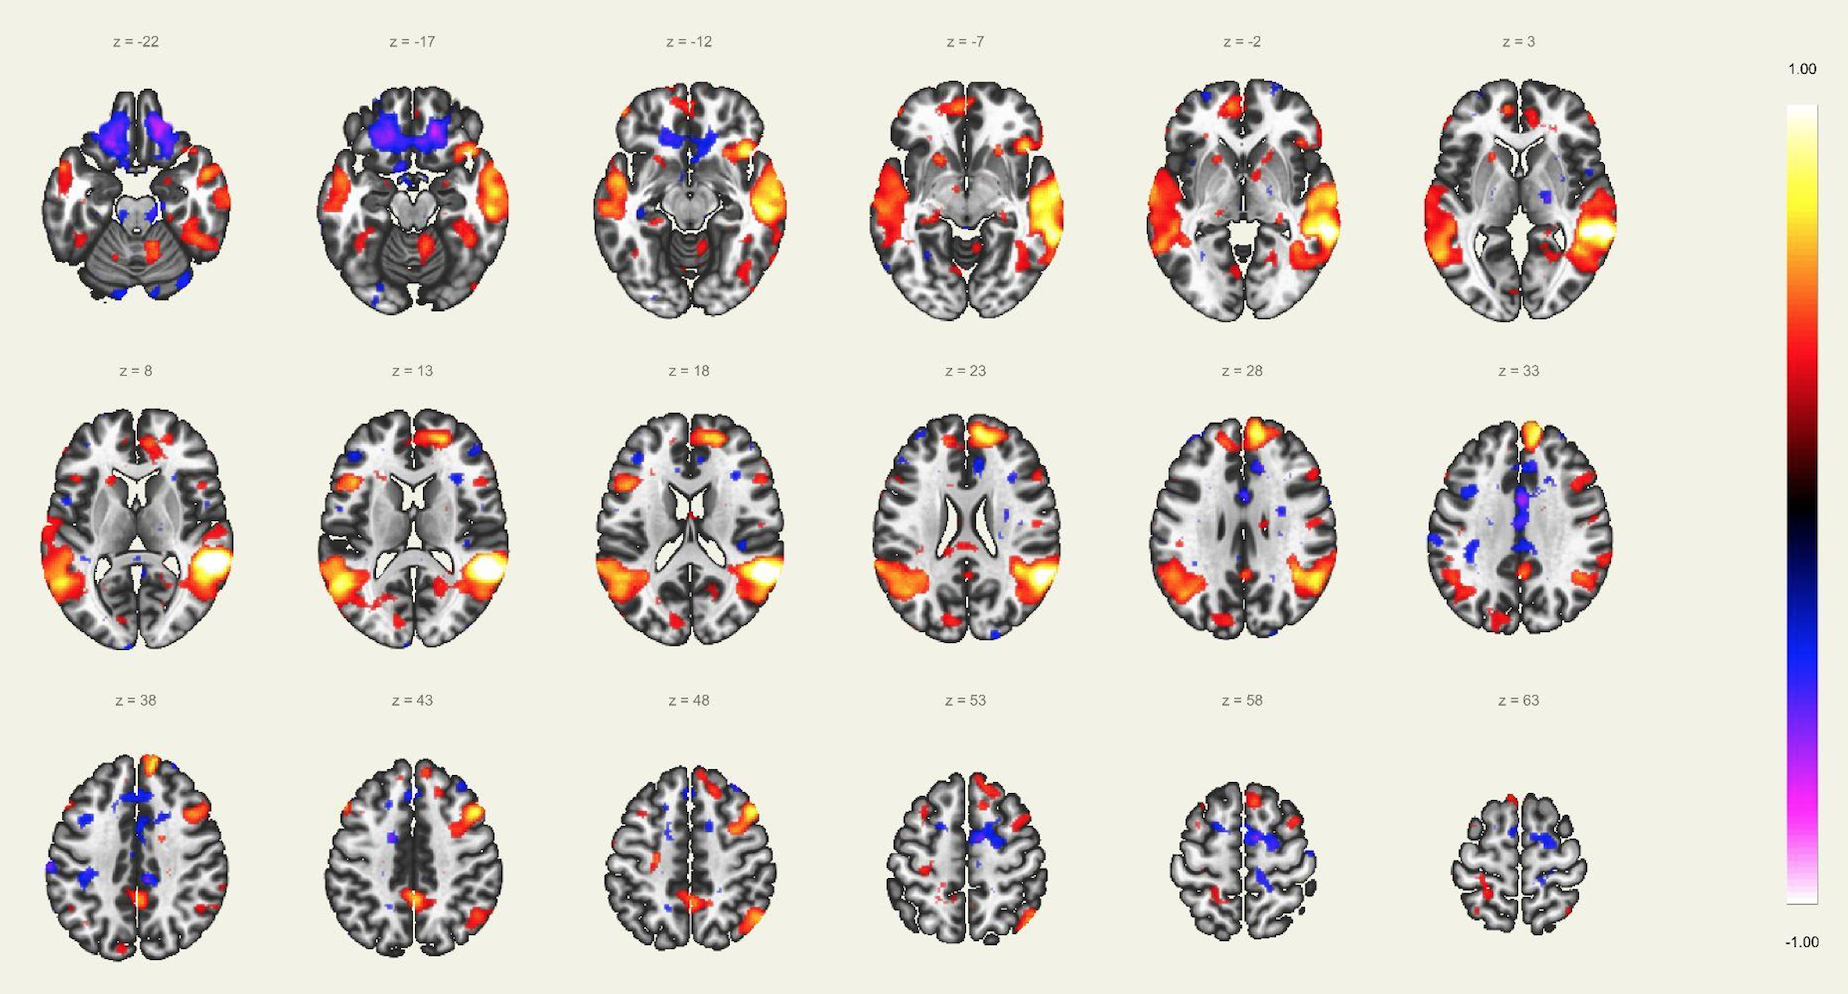

En este estudio, el escaneo se realizó con un resonador de 3 Tesla del servicio de diagnóstico por imágenes de la Clínica Internacional, a un paciente joven, sin comorbilidades ni antecedentes de importancia, el cual estuvo despierto en todo momento y con los ojos cerrados. Además, se le dio instrucciones de completar palabras mentalmente sin emitir sonido alguno o hacer gestos, llegando a identificarse las distintas redes cerebrales detalladas posteriormente.

El estudio fue realizado con secuencia BOLD, con los siguientes parámetros: cortes: 40, factor de distancia: 0%, Field of View: 240 mm, grosor de corte: 4 mm, tamaño de vóxel: 3.8 x 3.8 x 4 mm, TR: 3000 ms, TE: 30 ms, Umbral: 4 y tamaño del paradigma 20.

A pesar de la ausencia actividad física, resulta imposible indicar que no se esté realizando ningún tipo de actividad mental, como recuerdos o el uso de la imaginación. La consecuencia de esto se ve reflejada en los cambios de la actividad neuronal.16 A través de este método de vóxel semilla se ha logrado identificar distintas redes de conectividad funcional descritos a continuación:

Red Visual:

Se ha reportado la activación sincrónica en los surcos calcáreos, regiones extraestriadas, área inferior de la precuña y el núcleo geniculado lateral del tálamo, el cual se conecta funcionalmente con la corteza visual primaria en el lóbulo occipital. Estos a su vez se organizan en áreas visual medial (región extraestriada, división inferior de la precuña y núcleo geniculado lateral) y lateral (unión occipito temporal abarcando el polo occipital y la región parietal superior).

Red Visuo-Espacial:

Asociada a la red visual, compuesto por la corteza parietal posterior de la unión occipito parietal, región media de la precuña, corteza cingular posterior y el polo frontal, por lo que la afección de estas regiones puede afectar la atención espacial del individuo. Por lo que se infiere que la corteza parietal posterior está involucrada en orientarse hacia señales visuoespaciales sobresalientes.

Red “Modo por Defecto”:

Involucra la corteza cingular posterior, corteza prefrontal medial y la corteza parietal lateral. La actividad de esta red se ve incrementada en el caso de que la persona en estudio esté en una condición de reposo, observándose una especie de desactivación al realizar algunas tareas. Esta red tiene participación también en algunos aspectos sociales como la introspección, divagación, procesamiento emocional, entre otros.

Red Precuña:

Área asociada con la red “modo por defecto”, caracterizada con zonas de alta tasa metabólica comparado con otras redes durante el estado de reposo. Se ha reportado la importancia de esta área, interviniendo en funciones de comportamiento; así como en la manipulación de imágenes mentales y atención guiada internamente, derivada del estudio de imágenes visuoespaciales.

Red Auditiva:

Red asociada a la red sensorio motora, comprendido por la corteza auditiva primaria bilateral, giro temporal transverso, planum polare y temporale, giro temporal supero-lateral y corteza insular posterior. Las cortezas auditivas se encuentran bien definidas para como confiables para el giro temporal transverso de cada lado respectivamente.